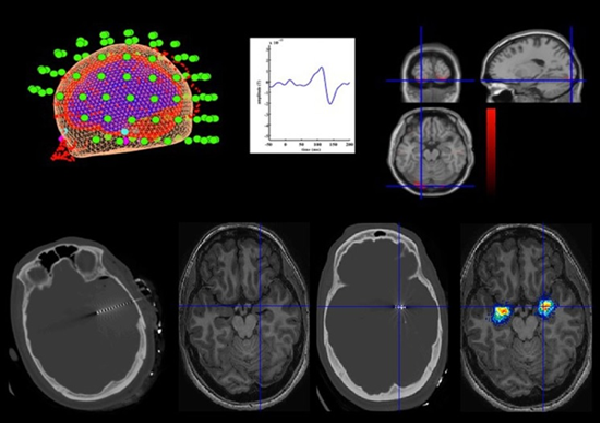

La magnetoencefalografía mide los campos magnéticos extremadamente débiles generados por la actividad eléctrica neuronal, principalmente por las corrientes postsinápticas de poblaciones de neuronas piramidales corticales. Estos campos atraviesan el cráneo y el cuero cabelludo prácticamente sin distorsión, lo que permite registrar la actividad cerebral con gran precisión temporal.

El sistema Cryo-MEG utiliza sensores superconductores SQUID (Superconducting Quantum Interference Devices), que son actualmente la tecnología de referencia en magnetoencefalografía.

Para alcanzar su máxima sensibilidad, estos sensores deben mantenerse a temperaturas criogénicas mediante helio líquido. Los sensores se encuentran integrados en un casco fijo que rodea la cabeza del participante, permitiendo registrar simultáneamente la actividad magnética cerebral en múltiples posiciones alrededor del cráneo.

- Investigación en epilepsia y localización de focos epileptógenos